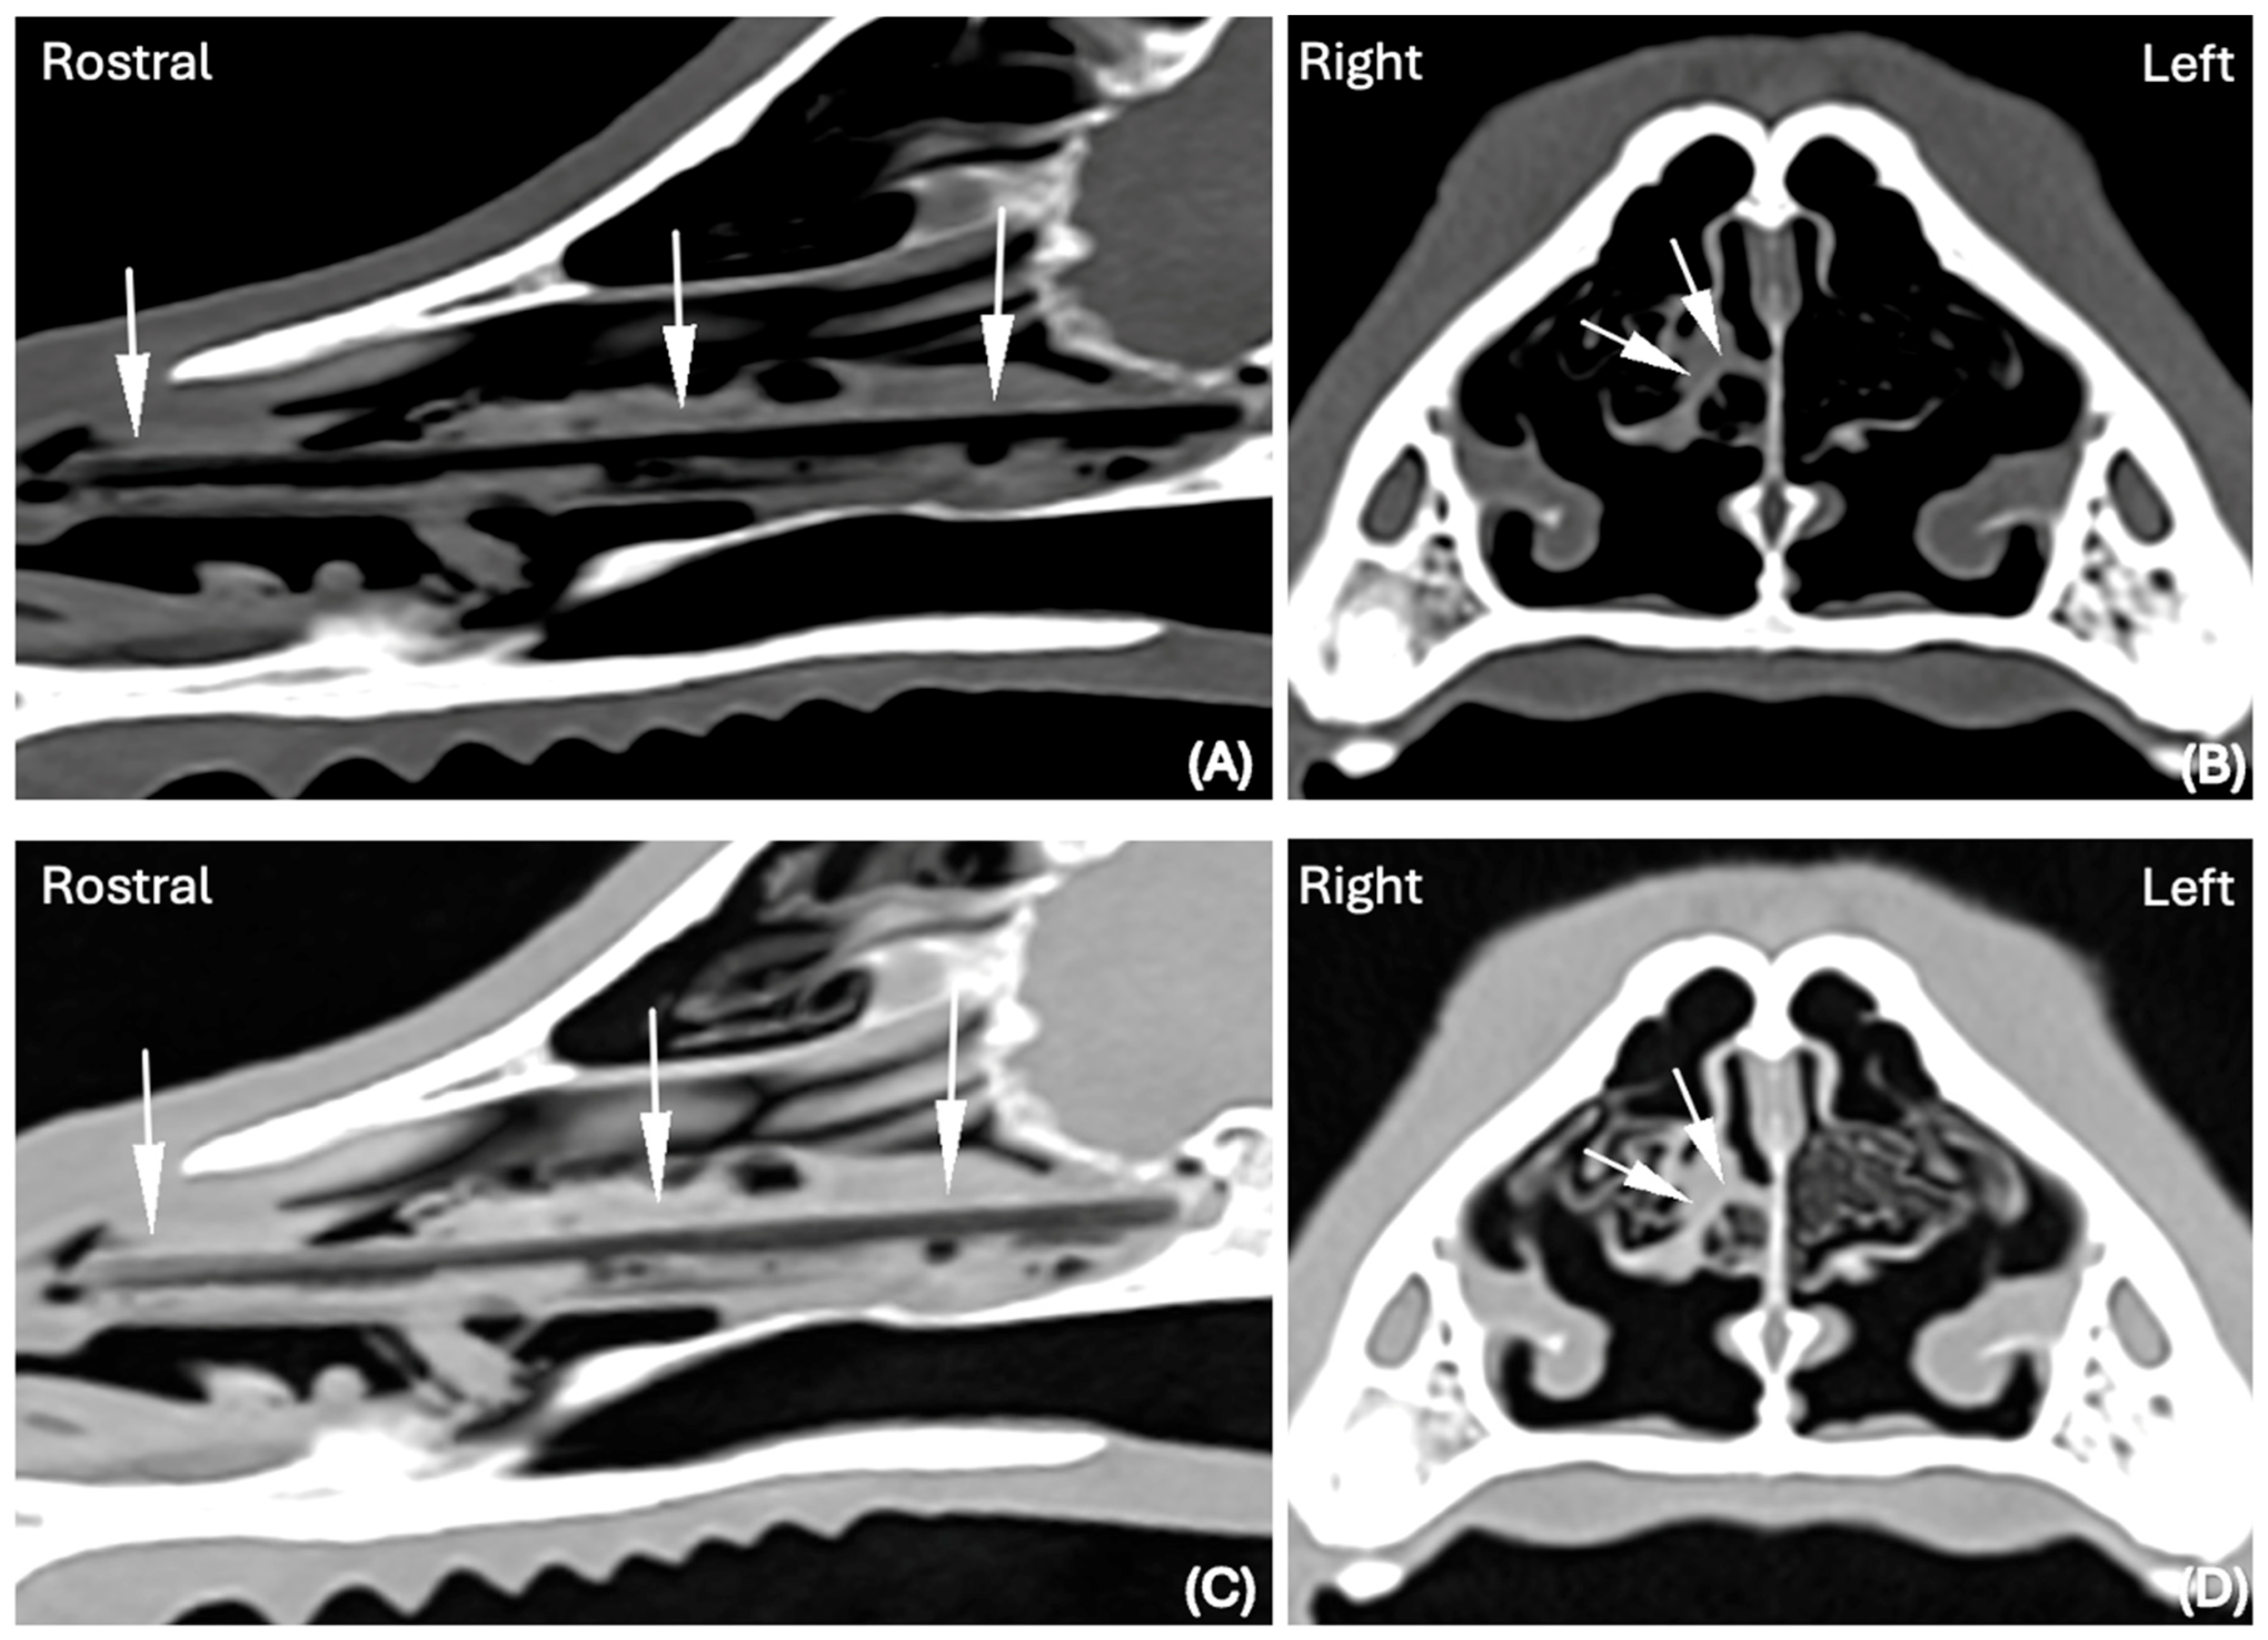

In one of 30 cases in which the nasal FB was considered suspicious in the BW (Figure 3A–C), it was subsequently confidently detected in the LW (Figure 3D–F).

In one case where the FB was considered “suspicious” in the BW, it was confidently detected when displayed in the LW, showing that using the latter might have achieved better delineation of its margins, as surrounded by air, and therefore its visualization in this isolated case (Figure 2).

Figure 3. CT images in (A) Sagittal, (B) Transverse and (C) Dorsal planar reconstruction, displayed in BW (WL 300 HU, WW 1500 HU); scale (DPI 144 × 144). CT images in (D) Sagittal, (E) Transverse, and (F) Dorsal planar reconstruction displayed in LW (WL −500 HU, WW 1400 HU); scale (DPI 144 × 144) of the same dog (Labrador, 8 years old, MN), of the rostral third of the nasal cavity. The presence of a nasal foreign body was considered suspicious in BW (white arrows) (AC). In the LW, a well-defined thin elongated foreign body was clearly identified (white arrows) (DF). A grass blade was successfully retrieved via rhinoscopy.